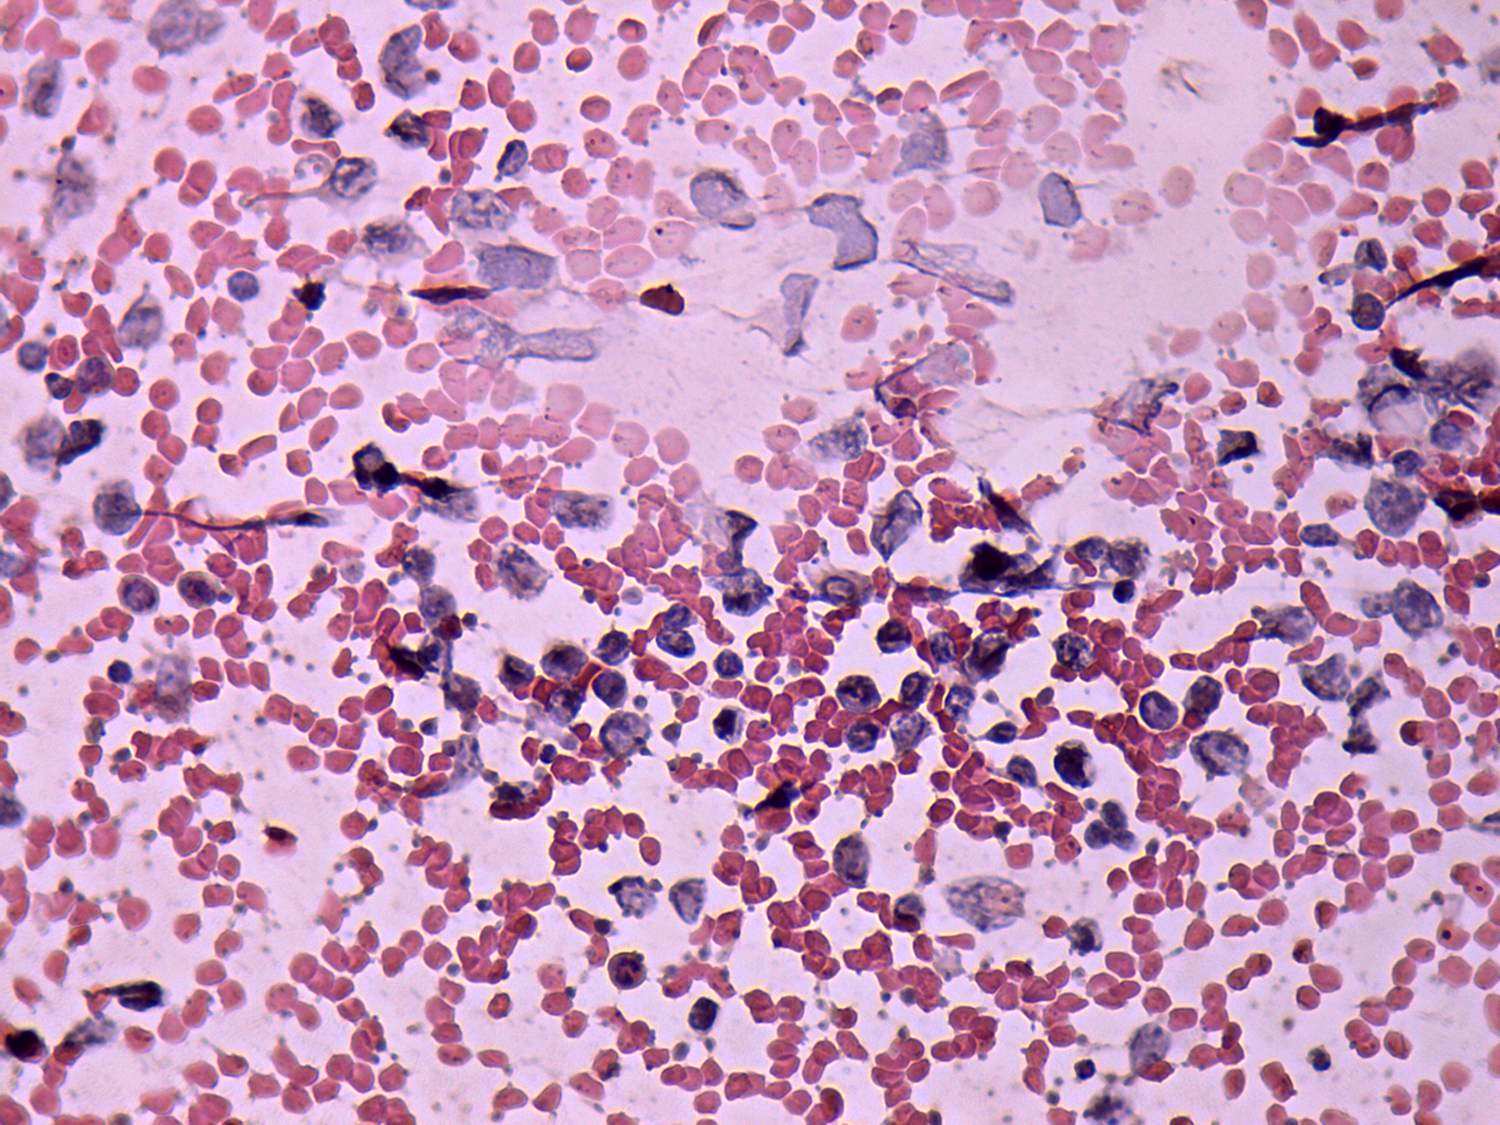

Pap-smear, 400x.   Heterogeneous lymphoid cells with relatively great proportion of lymphoblasts.